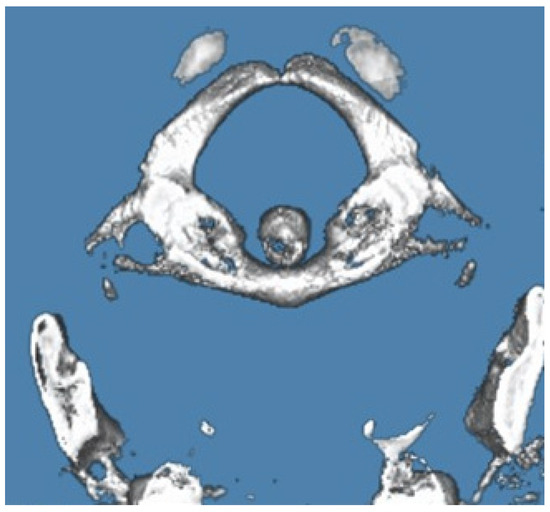

3.2.2. Case Report 2: Unilateral Partial Ponticulus Posticus and Partial Atlantal Posterior Arch Defect Type A in a 54-Year-Old Female: Clinical Presentation and Imaging Characteristics

| 2 | 54 years | Partial APAD | Unilateral Partial | Mild to moderate neck pain; intermittent tingling in right upper limb | Physical therapy and NSAIDs; follow-up imaging recommended | Symptoms improved; no significant defect progression |